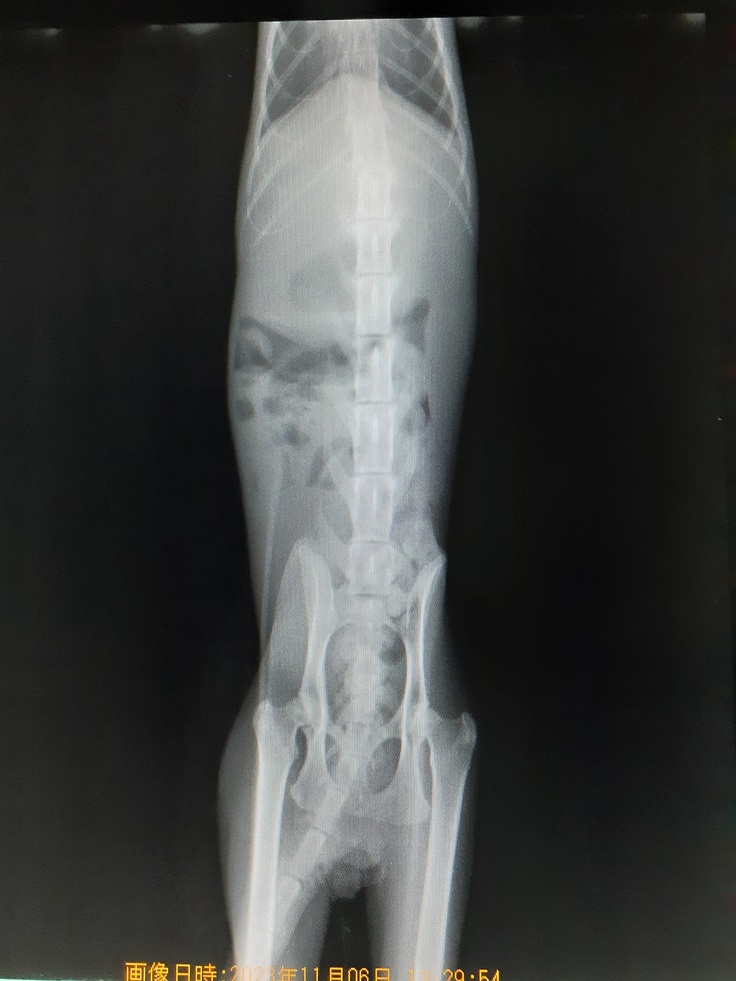

下半身不随の状態もレントゲンにて確認してきました。

背骨の3つと4つ目の骨が骨折していました。

既にねこ活にいる下半身不随の【くるみちゃん】は3つ目の骨折でしたのでそれよりは酷い状態を確認いたしました。

病院では大分酷い事故であったことを血液検査、レントゲンにて説明していただきました。